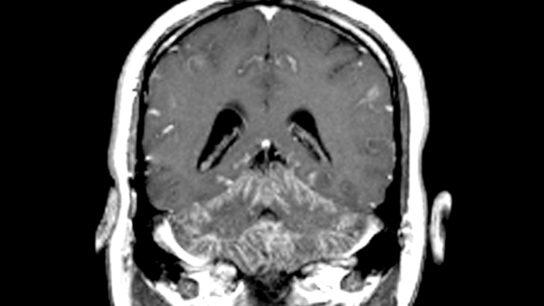

While immunocompromised patients are the most susceptible to CNS fungal infections, they can also occur in immunocompetent patients undergoing invasive procedures such as neurosurgery and in patients exposed to contaminated devices or drugs.